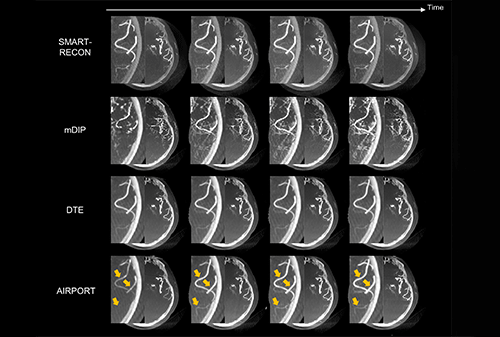

IEEE TMI | High Time Resolution CT Imaging

Recently, researchers Li Yinsheng and Liang Dong from the Medical Artificial Intelligence Research Center of Shenzhen Institute of Advanced Technology, Chinese Academy of Sciences, and the Key Laboratory of Medical Imaging Science and Techn...